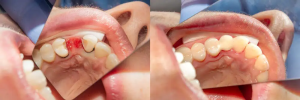

Sebelum & Sesudah Tindakan (Before – After)

Sumber: https://santarosaoralsurgery.com/wp-content/uploads/2021/08/santa-rosa-impaction-bracketing-1.jpeg